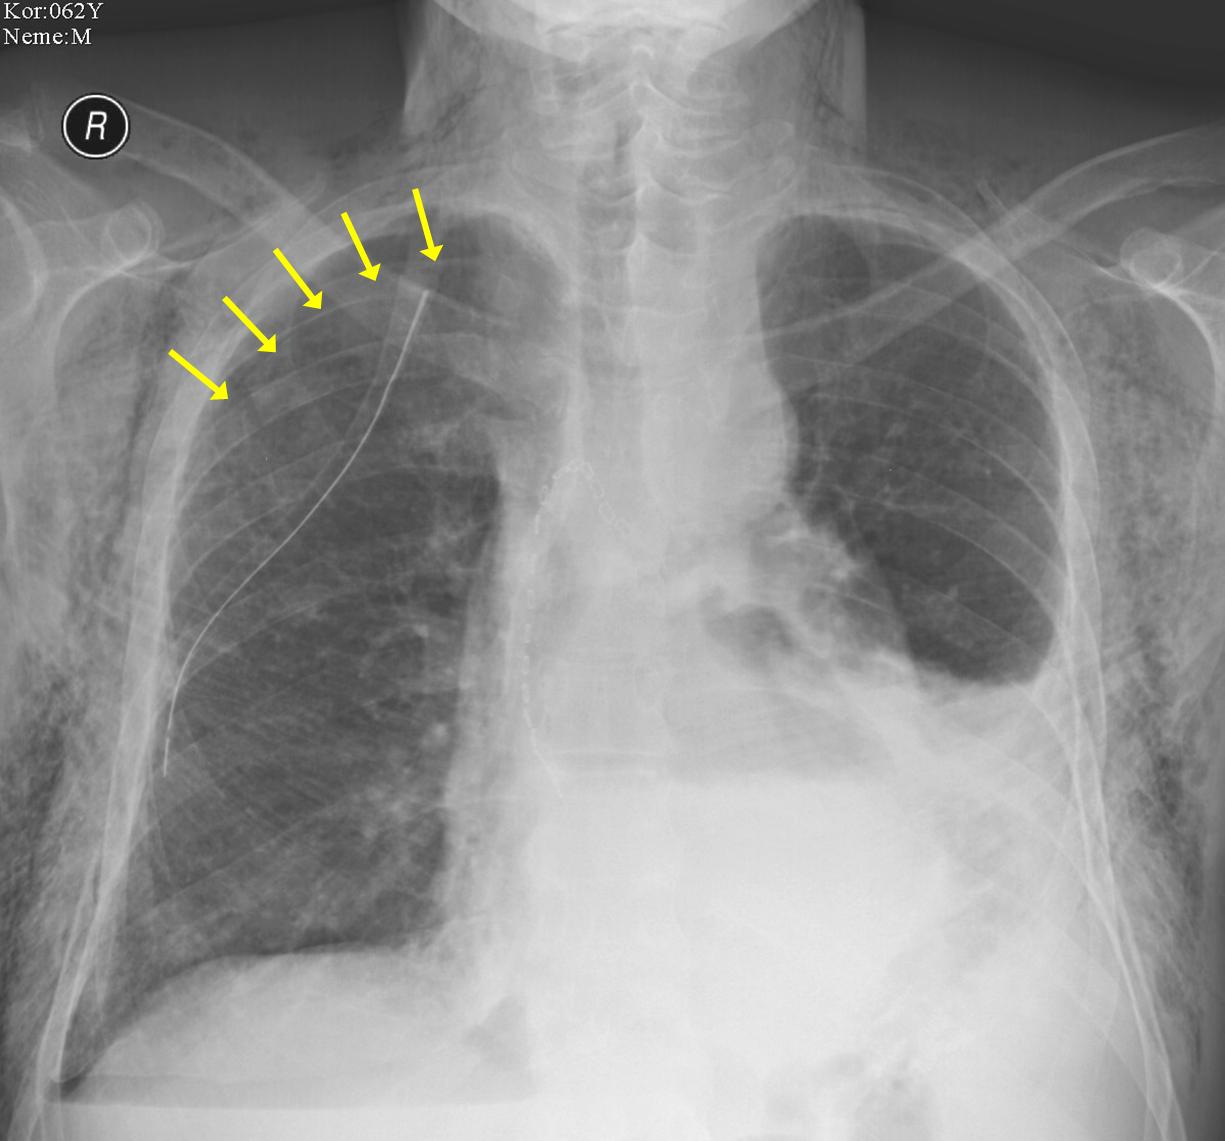

• Pneumothorax usually occurs following thoracic trauma, but it can also happen spontaneously. The same also applies for the appearance of mediastinal air. The most severe form of ptx is tension- pneumothorax that inflates the pleural cavity with each breath, as the air remains trapped due to the valve mechanism of the injury. Conventional chest radiography is sufficient for the diagnosis.

• Hydrothorax occurs as a consequence of certain pathologic states as the pleural cavity fills with fluids and causes compression of the lung and ventilation deficit. At most cases it can already be revealed with chest radiography. Sonographic examination can also be diagnostic, moreover it is able to give further information about the fluid’s characteristics and detect septations. The latter is valuable information for the clinician if drainage is considered.

• ARDS: adult/ (acute) respiratory distress syndrome is a complication of the severely ill, usually ICU patients. It results in the severe loss of lung capacity. Diffuse alveolar injury leads to fluid leakage into the alveolar spaces that first appear as distinct alveolar consolidations. Later, they evolve to confluent patches of opacity (snow storm appearance).

14. Typical appearance of ARDS on chest X-ray: massive, bilateral consolidations with aerobronchograms.

• Pneumonia can also be detected with radiography. However, one must consider that on unidirectional chest radiographs, lung areas behind the heart and the diaphragm are obscured and infiltrates can remain hidden. To overcome this, a lateral radiograph should also be taken. However, as a first step clinicians should indicate the side on which the infiltrate is suspected, since this affects the radiologist’s decision making about which side of the chest should be set closer to the detector for better visualization and diagnosis.

• Pulmonary embolisation should be investigated with pulmonary CT angiography examination. Conventional chest radiography is negative in the majority of the acute cases. Indirect signs, such as pleural effusion, ipsilateral elevated diaphragm, atelectases or infarct pneumonia only appear after a longer period of time. As opposed to this, CTA provides a swift and precise diagnosis.